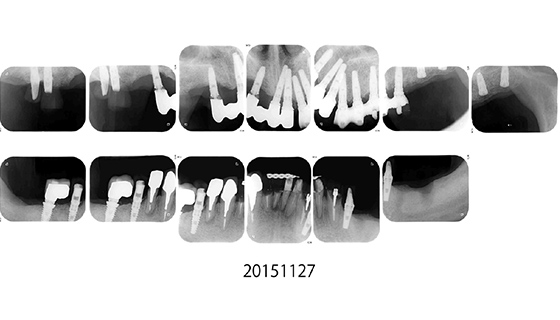

治療経過

オールオン4が存在しなかった2007年当時に、インプラントでの治療を行いました。当初の治療プランとしては、既に欠損している左下にインプラントを施して左側で噛めるようにし、次に崩壊が進んでいる右上にインプラントを埋入、その後に上前歯という順番で噛み合わせの高さと噛む機能を維持した状態で噛み合わせの崩壊を防ぐ、という計画でした。

2000年と2003年の文献で一番成功率が高いと評価されたイノバ社のエンドポアインプラントを使用して治療を行いました。

右下の奥歯

一通り治療が終了した後、右下の奥歯が根の周囲に膿を溜めて強い痛みを起こしたため、抜歯し、インプラントをしました。この時は、国産のGCインプラントを使用しました。

右上犬歯

犬歯ということで大きな負荷がかかった為か、インプラント周囲の感染か、糖尿病のせいか、喫煙の影響か、右上犬歯分のインプラントが脱落したため、インプラントで最も古い歴史を持つブローネマルクインプラントを埋入しました。